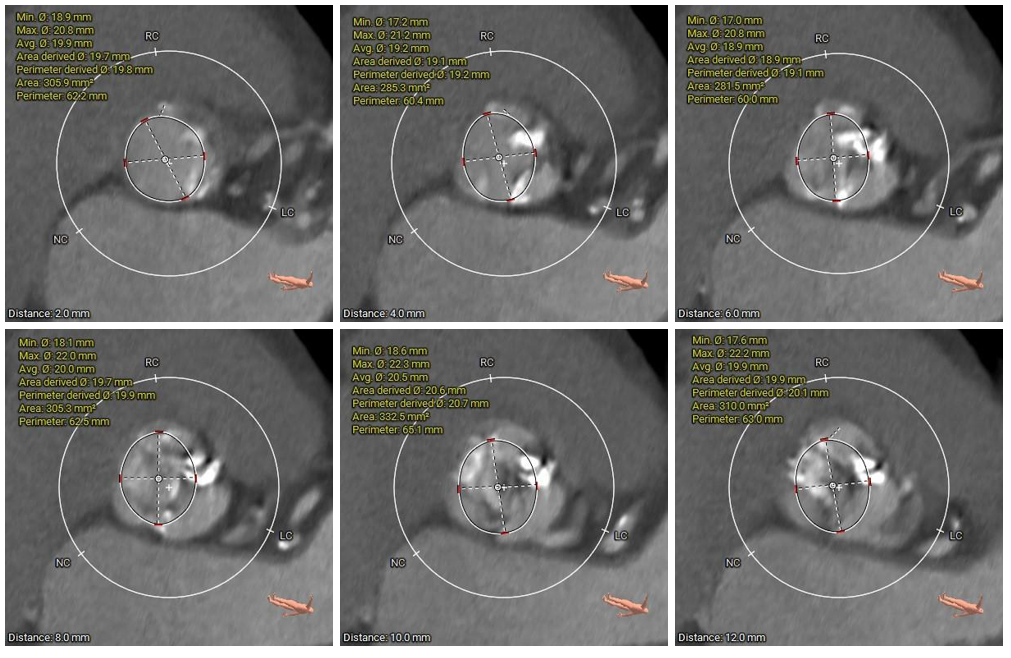

术前CT评估

• Type1型二叶式主动脉瓣,瓣叶增厚伴中重度钙化,左右窦间可见钙化融合嵴;LVOT呈类直筒型;

• 左冠脉开口高度较低,右冠脉开口高度尚可,切线位左冠瓣叶长度>冠脉开口到瓣叶附着缘距离;左冠脉可见少量钙化;

• 瓦氏窦、窦管交界内径偏小、升主动脉内径可;左室腔内径偏小,心室壁明显增厚;

• 瓣环平面与水平夹角为48°,主动脉弓弓距及夹角尚可;

CT动态预览

主动脉根部测量